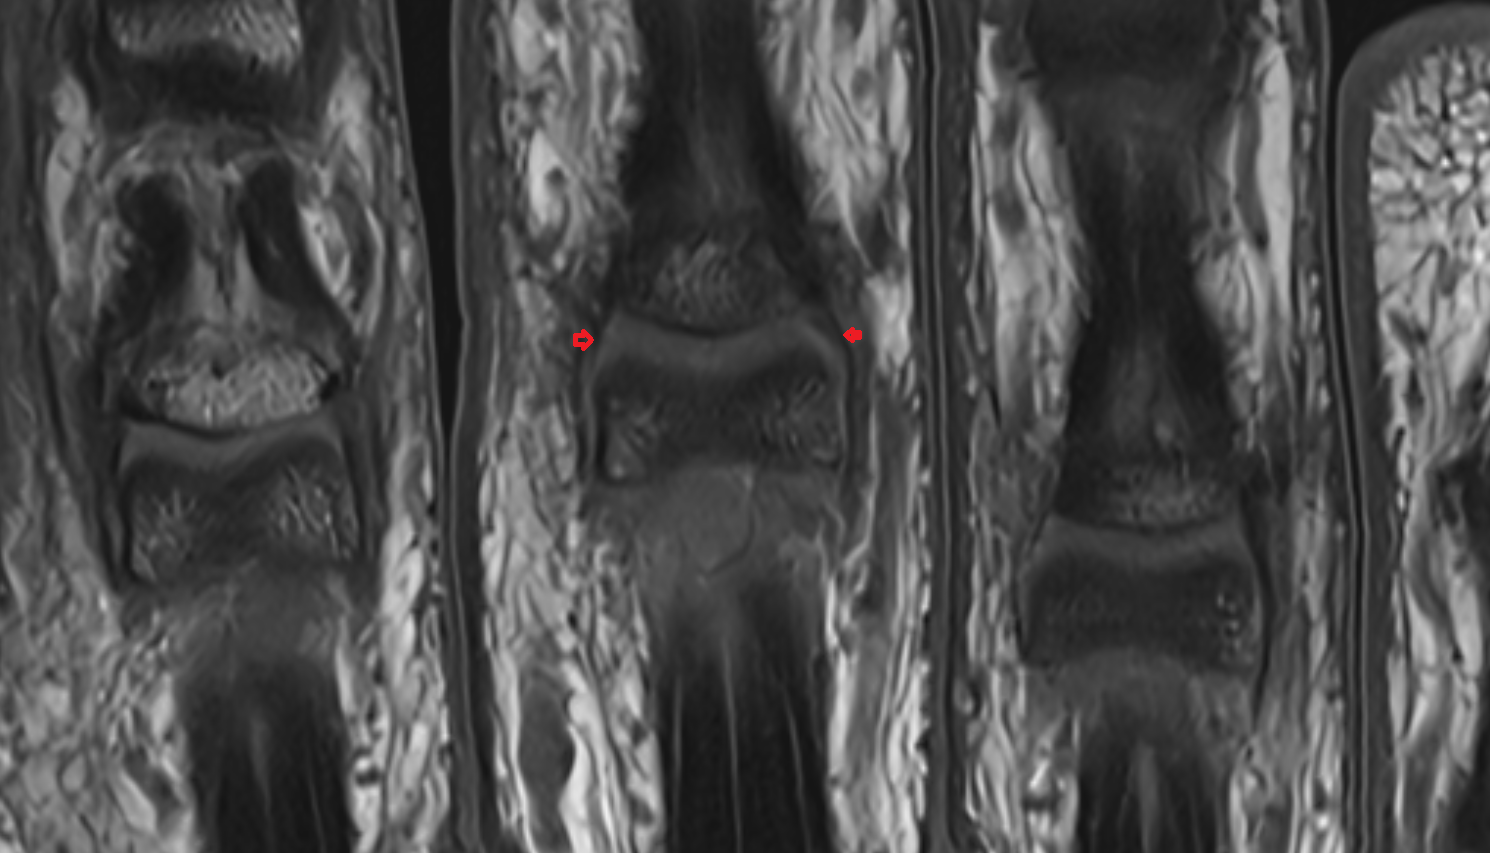

- Medial meniscus

- Lateral meniscus